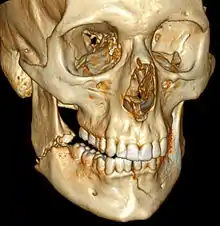

3D computed tomographic image of a mandible fracture in two places. One is a displaced right angle fracture and the other is a left parasymphyseal fracture. | |

Computed tomography is the most sensitive and specific of the imaging techniques. The facial bones can be visualized as slices through the skeletal in either the axial, coronal or sagittal planes. Images can be reconstructed into a 3-dimensional view, to give a better sense of the displacement of various fragments. 3D reconstruction, however, can mask smaller fractures owing to volume averaging, scatter artifact and surrounding structures simply blocking the view of underlying areas.

- 3D CT reconstruction of mandible fracture, white arrow marks fracture, red arrow marks moderate displacement and open bite